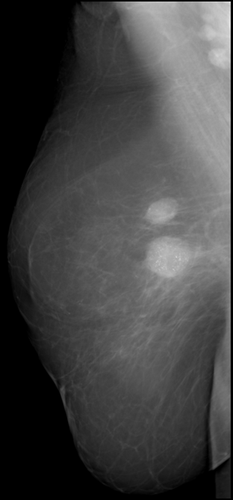

Аномалии молочной железы: медицинские примеры и визуализация

Раздел: Мудрость в деталях